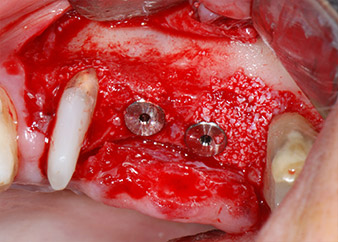

Gli impianti (Restore, Keystone Dental,, diametro 3,75 mm, lunghezza 8,0 mm) sono stati posizionati con il motore per impianto (Figg. 11 e 12).

Le mancanze di tessuto osseo attorno gli impianti, in corrispondenza dell'aspetto mesiale del dente 27 e attorno alla radice buccale del dente 24, sono stati riempiti con particelle xenogeniche di sostituzione ossea e coperte con una membrana di collagene assorbibile (Bio-Gide, Geistlich Biomaterials) per tecnica di innesto GBR (Figg. 13 e 14).